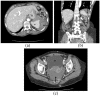

Splenic laceration is a rare yet often underreported complication of colonoscopy that is infrequently discussed with the patient during the consent process. Most cases present within 48 h after the inciting colonoscopy; a delayed presentation is rare. We present a case of splenic laceration with hemoperitoneum that manifested 5 days after the initial colonoscopy. The patient was treated conservatively. Traditionally perceived risk factors such as intra-abdominal adhesions, splenomegaly, anticoagulation use, biopsy, polypectomy, a technically challenging procedure, and anesthesia assistance have not been clearly shown to increase the incidence of splenic injury following a colonoscopy. Since the risk factors of splenic injury remain unclear, the clinical presentation is nonspecific, and the consequences can be serious, the endoscopist should make an effort to inform the patient of this rare complication before the procedure.